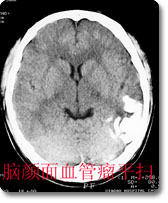

中枢神经影像诊断是本科室的特色、强项诊断之一,尤其是现代影像学诊断,如CT、MRI等,是西南地区最早开展此项工作的单位,积累了丰富的临床经验,有较高的诊断水平。如对脑肿瘤的影像学表现和肿瘤分子生物学基础的对照研究、脑血管病的诊断和介入治疗等在国内处于领先地位。 |